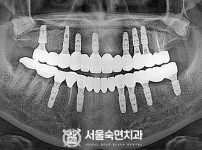

상악동거상술, 뼈이식 / 숙면임플란트 13개 - 오스템임플란트 (이*웅님)

해당 게시물은 의료법 제56조에 의거하여 로그인 후 열람이 가능합니다.

구분 임플란트